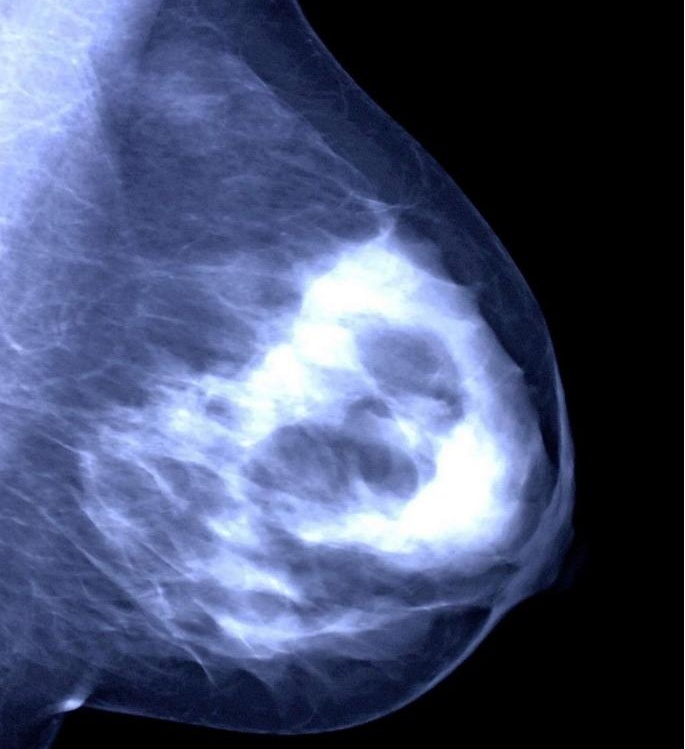

①乳腺超声:就像给乳房做“B 超体检”,能清楚看到肿物的大小、形状、边界等,是最常用的检查方法。

②乳腺钼靶:有点像给乳房拍“X 光片”,能发现一些超声看不到的细小钙化,对40岁以上女性筛查乳腺癌很有帮助。